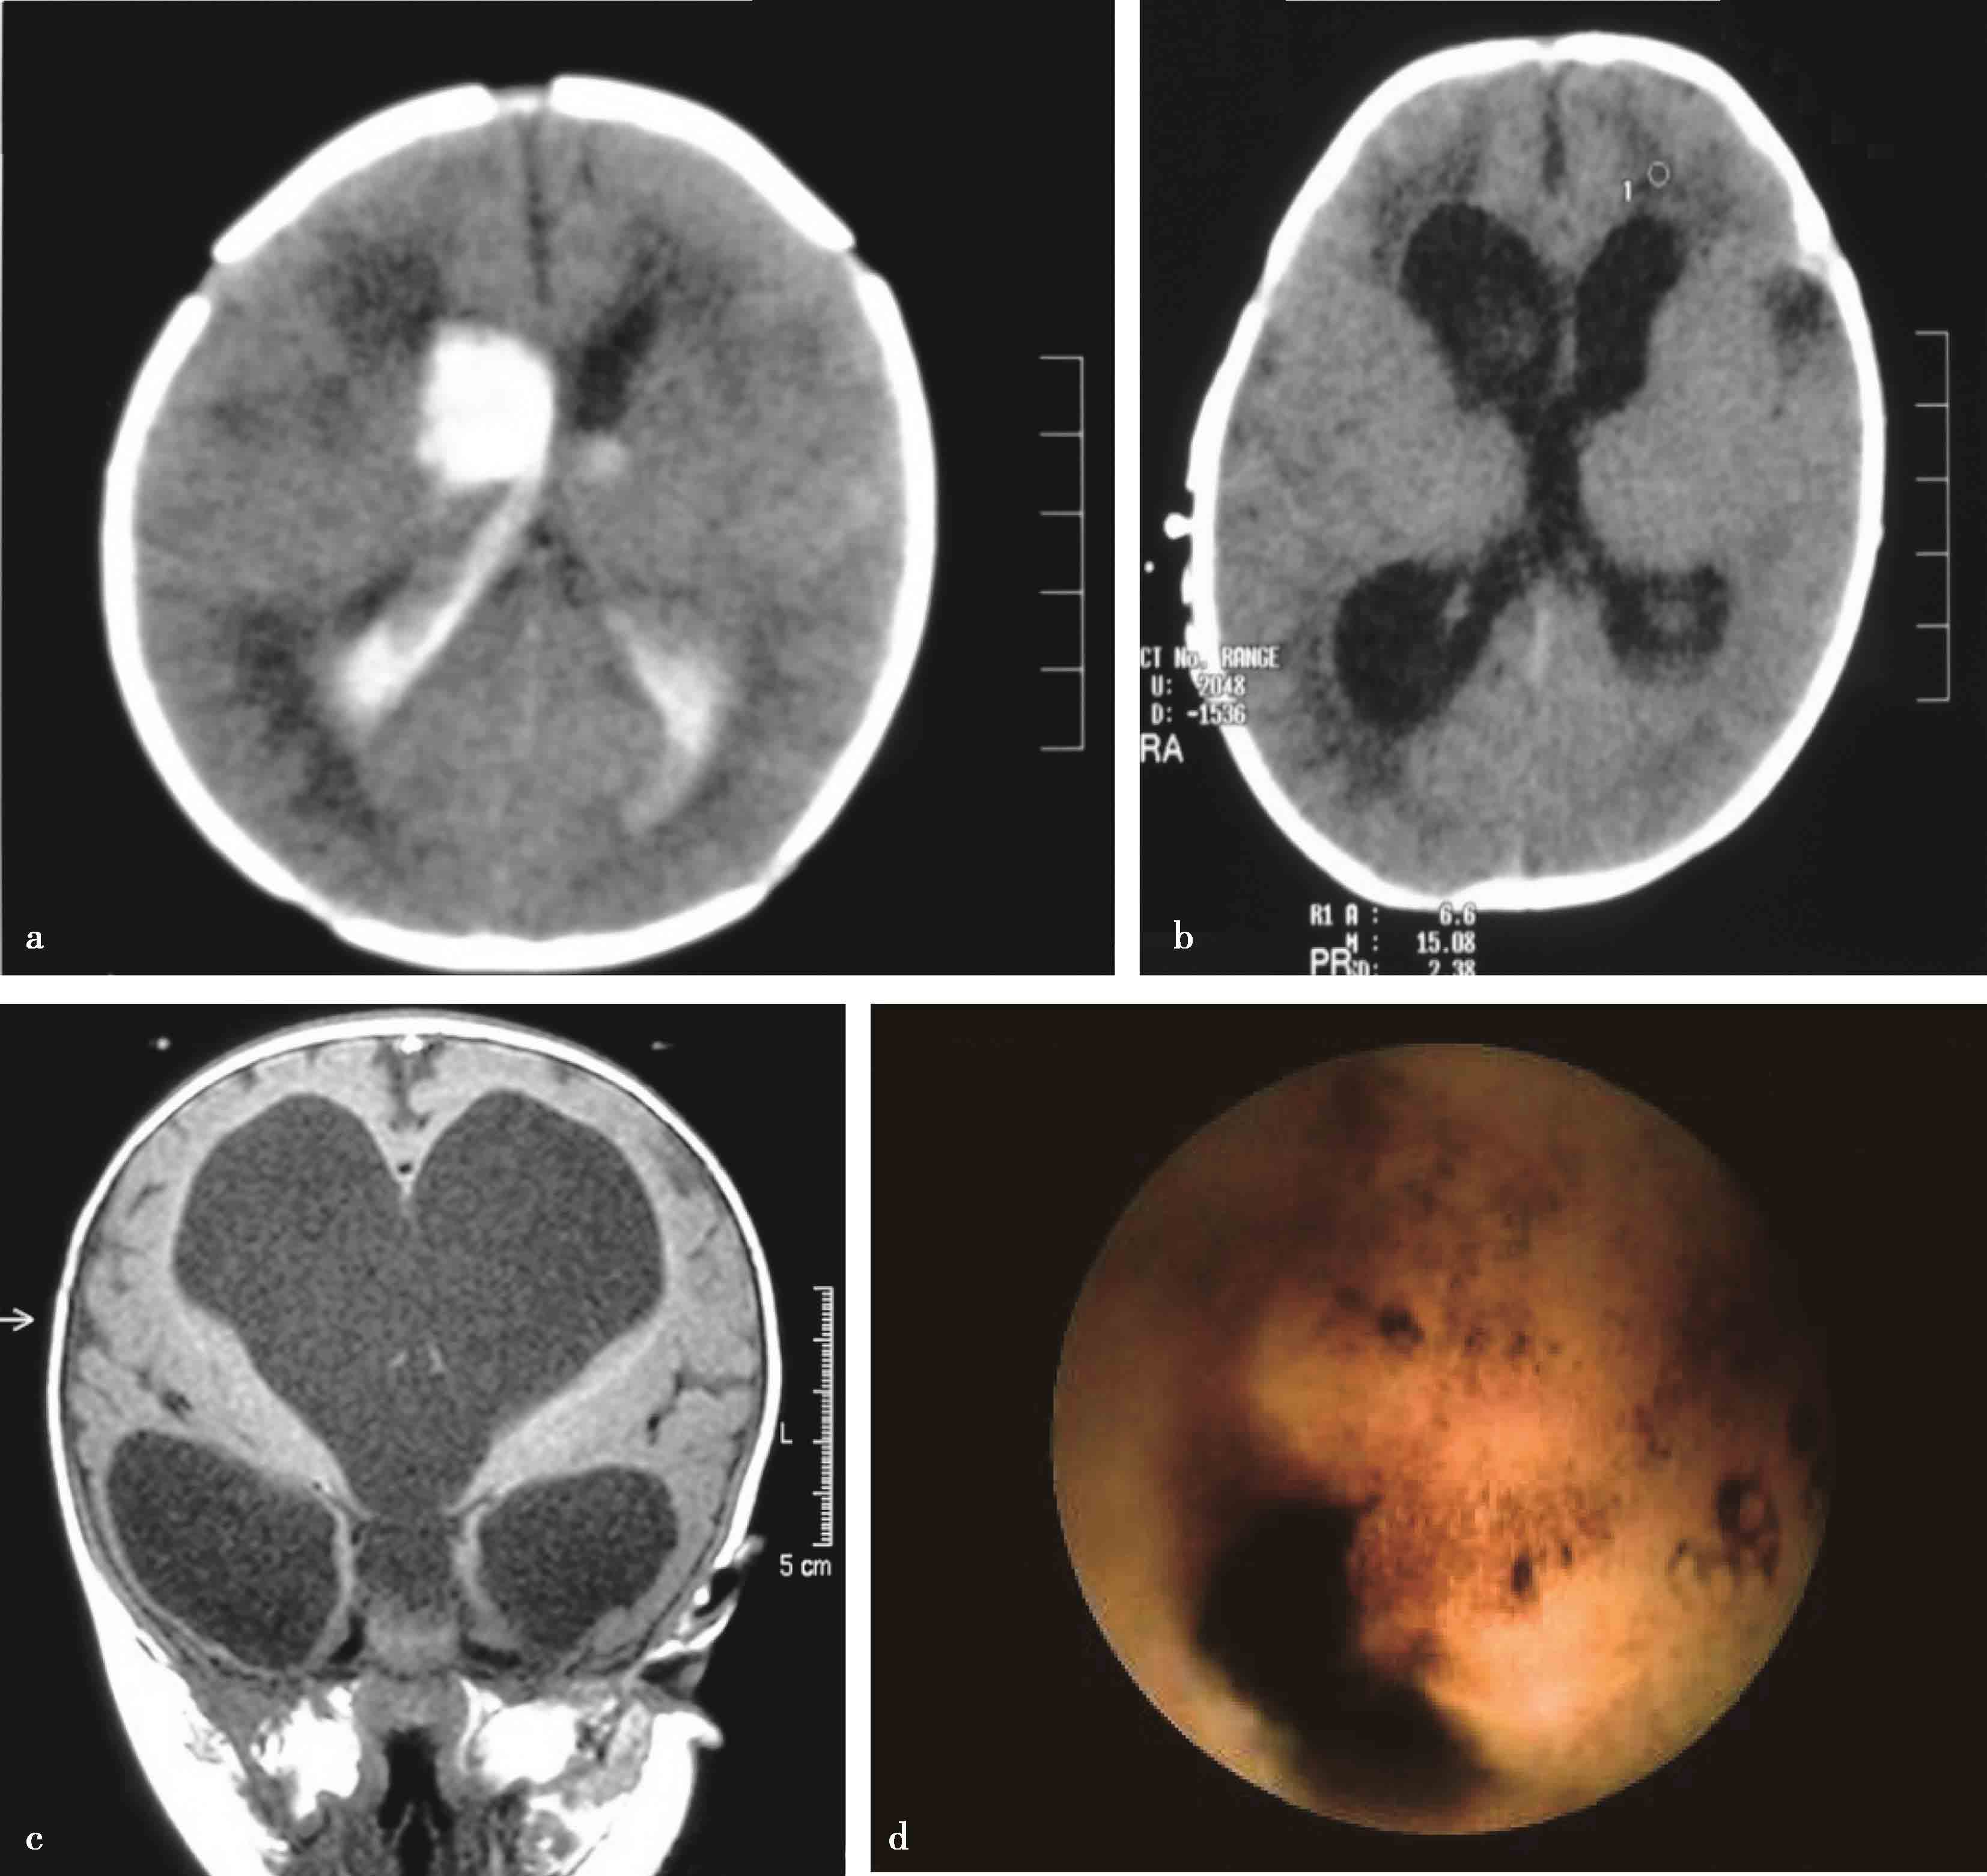

图3-1-1-4 感染后脑积水内镜下探查所见

a.脑室壁上的菌斑;b.脑室内结核所致干酪样坏死物;c.脑室内真菌感染;d.第四脑室内囊虫